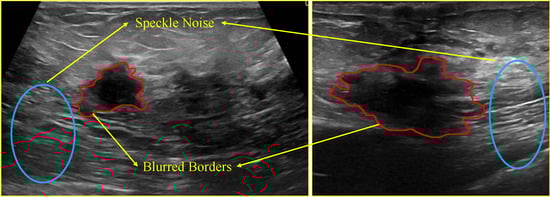

Breast tumors are a prevalent health concern for women that significantly impacts their well-being and lives. As a result, regular breast screening and diagnosis play a crucial role in formulating effective treatment plans and improving survival rates. Due to the flexibility and convenience of ultrasound imaging, it has become a conventional modality for breast tumor screening. In recent years, many deep learning methods based on ultrasound images have been proposed for breast tumor segmentation. However, complex ultrasound patterns continue to pose the following challenges: (1). blurred boundaries caused by low contrast between the foreground and background; (2). segmentation disruption due to speckle noise (as illustrated in Figure 1).

Figure 1. Challenges in a breast ultrasound image segmentation task. The red lines are the boundaries of the breast tumors. Inside and outside the boundaries are where the boundaries are blurred. The areas inside the blue circles are typical regions of speckle noise, which refers to irregular, distinct brightness and darkness distribution.